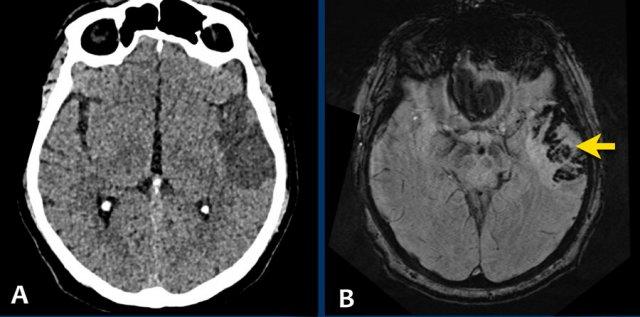

Bệnh nhân này nhập viện với não úng thủy do xuất huyết não thất (hình bên trái).

Lưu ý vùng tăng tỷ trọng rất nhỏ tại đồi thị trái, là điểm khởi phát của xuất huyết.

Theo dõi một ngày sau (hình bên phải).

Bệnh nhân được phẫu thuật đặt dẫn lưu não thất để điều trị não úng thủy.

Lưu ý đồi thị bên trái giảm tỷ trọng với ổ tăng tỷ trọng dai dẳng ở vị trí trong.